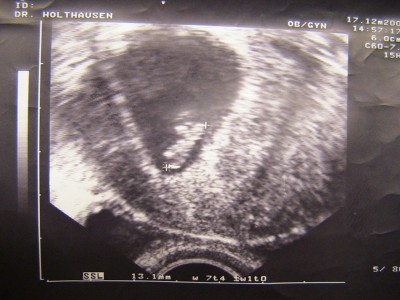

Wie Susi,euch ja schon berichtet hatte bin ich mir Blutungen ins Kh ich hatte mega grosse Angst meine Beine zitterten so das der doc schon sagte halten sie mal die beine ruhig aber es ging nicht ,auf dem US war dann die Fruchthülle zu sehen .Dann endlich ein paar Tage später war der Herzschlag zu sehen ich lag auf dem stuhl und fing bitterlich an zu weinen mein Mann war auch dabei er hat auch Tränen in denn Augen.Ich muss mich schonen darf nicht schwer heben.Oh Mann ich hoffe es geht jetzt alles gut!Am Montag muss ich zu meinem Frauenarzt